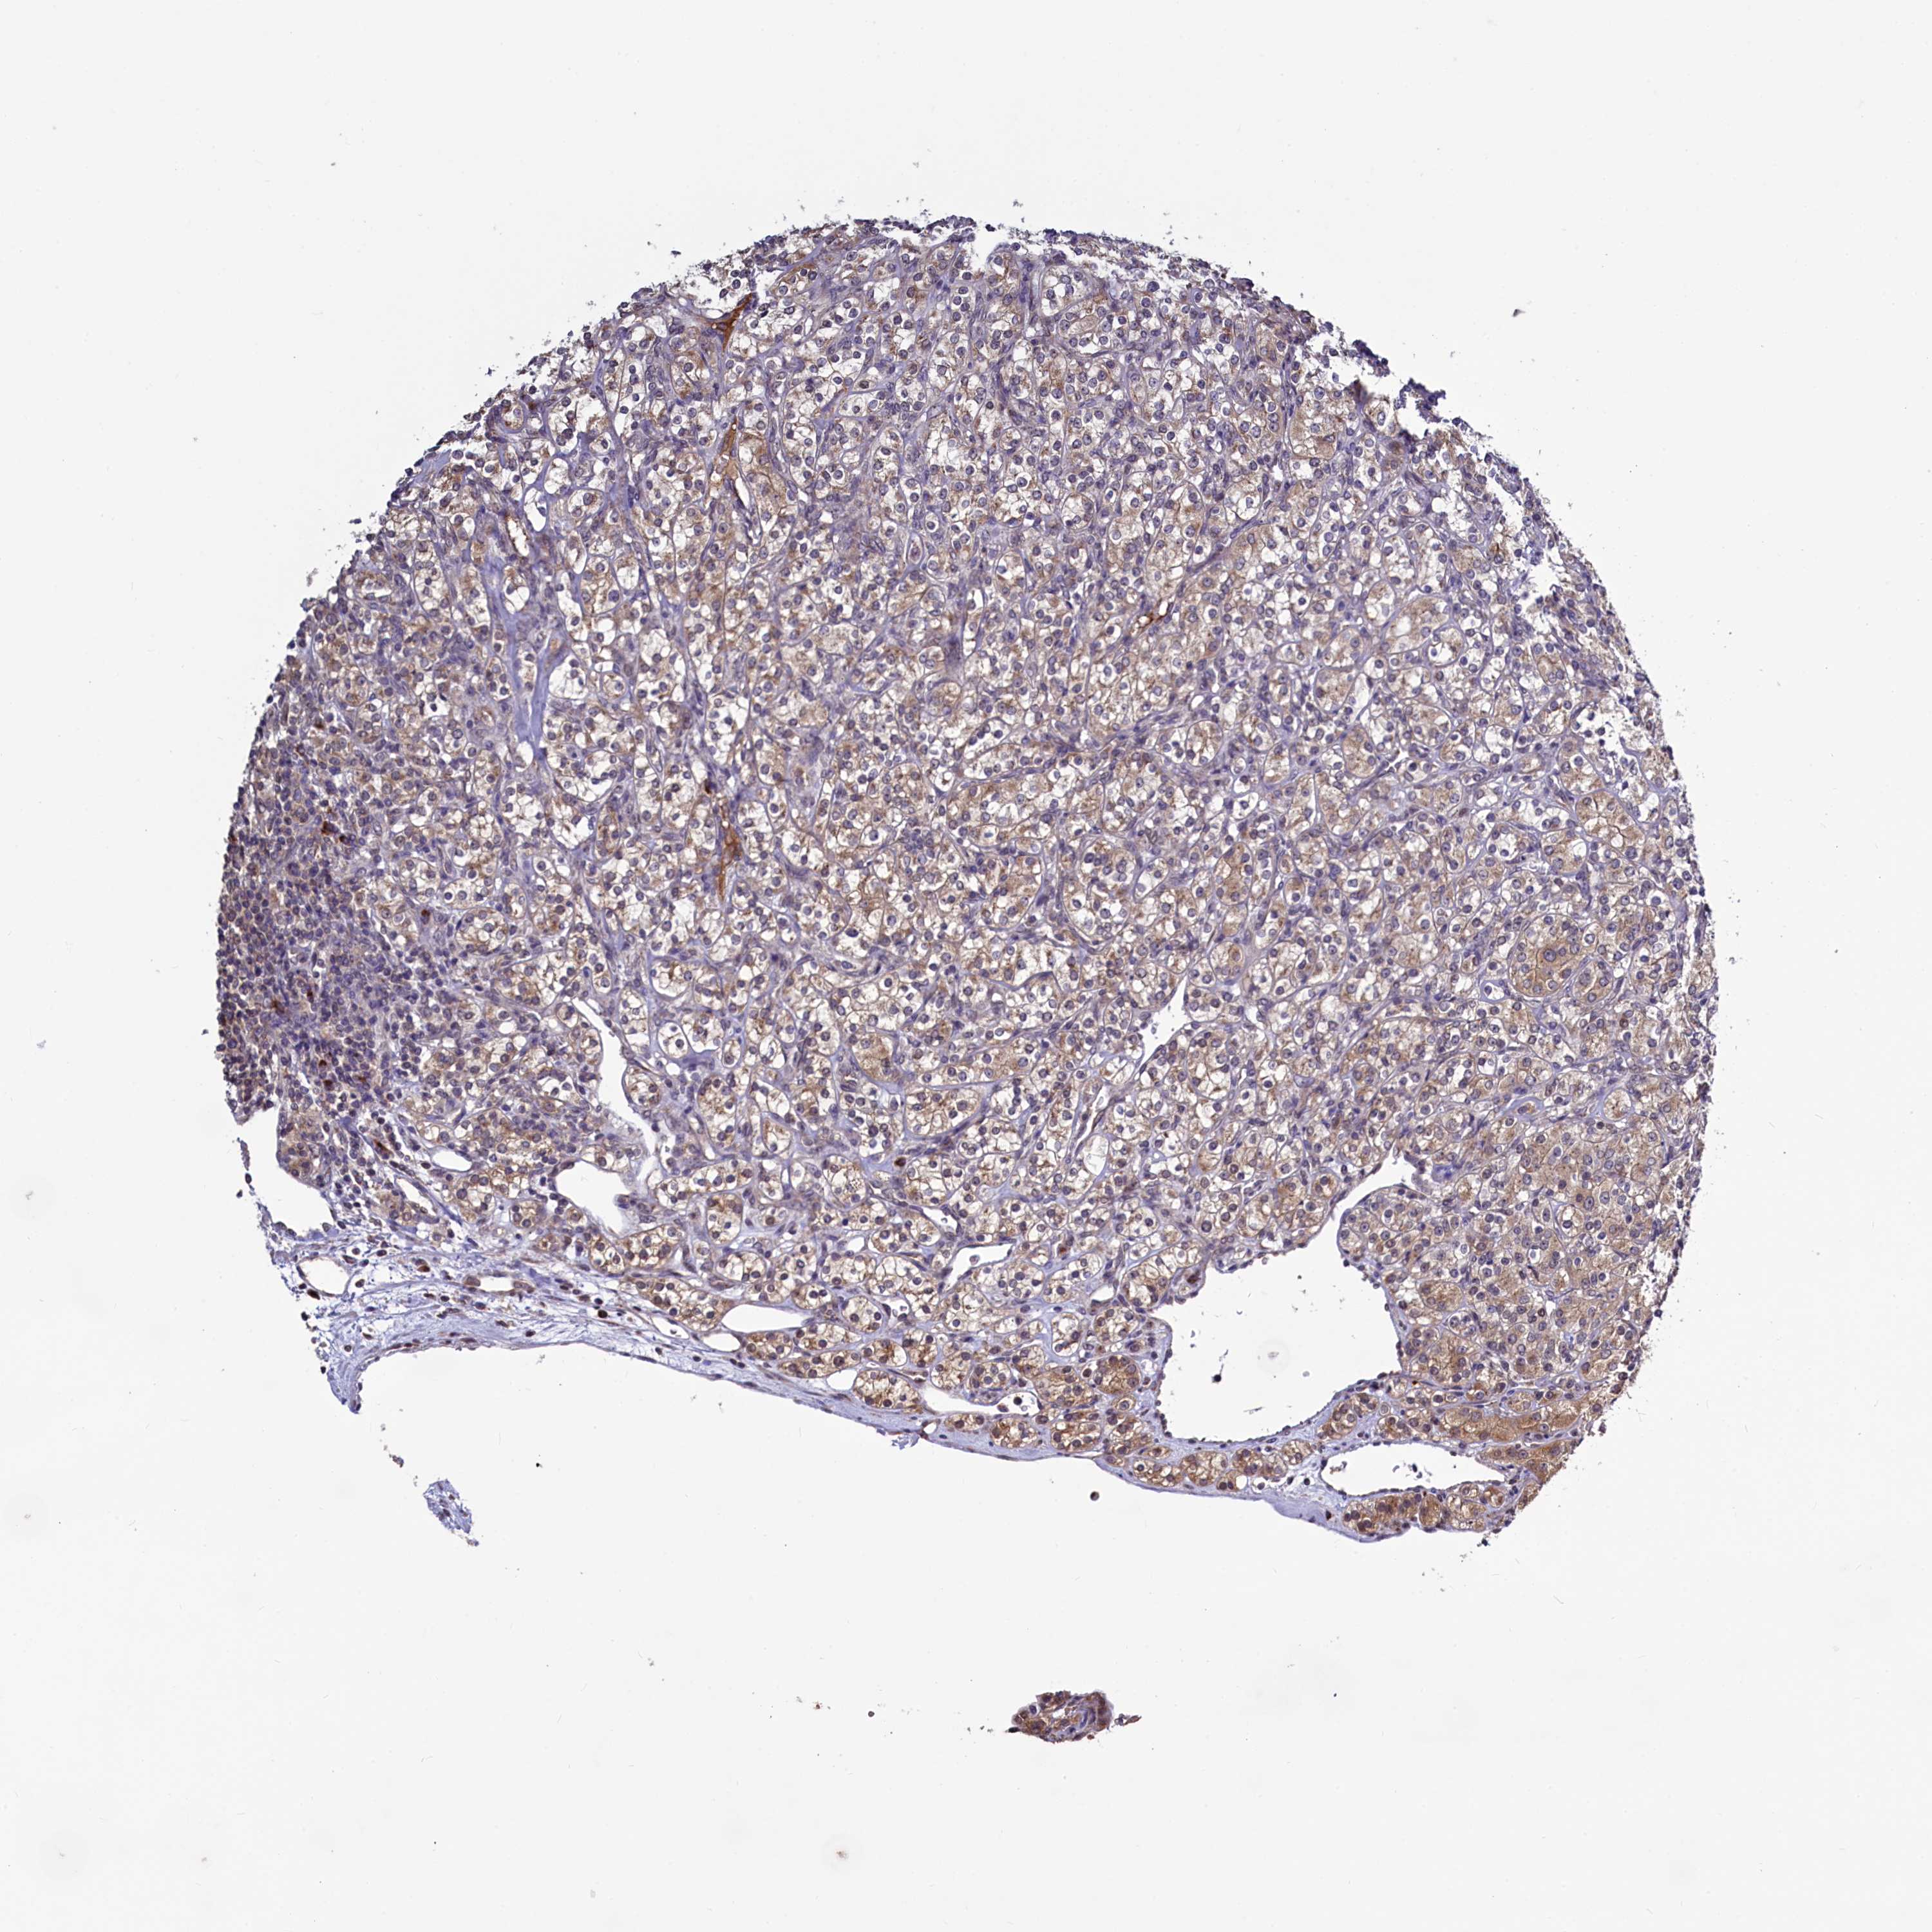

KIDNEY RENAL CLEAR CELL CARCINOMA (VALIDATION) - Interactive survival scatter ploti

The Survival Scatter plot shows the clinical status (i.e. dead or alive) for all individuals in the patient cohort, based on the same data that underlies the corresponding Kaplan-Meier plots. Patients that are alive at last time for follow-up are shown in blue and patients who have died during the study are shown in red.

The x-axis shows the expression levels (FPKM) of the investigated gene in the tumor tissue at the time of diagnosis. The y-axis shows the follow-up time after diagnosis (years). Both axes are complimented with kernel density curves demonstrating the data density over the axes. The top density plot shows the expression levels (FPKM) distribution among dead (red) and alive patients (blue). The right density plot shows the data density of the survived years of dead patients with high and low expression levels respectively, stratified using the cutoff indicated by the vertical dashed line through the Survival Scatter plot. This cutoff is automatically defined based on the FPKM cutoff that minimizes the p-score. The cutoff can be changed by dragging the vertical line or by entering a cutoff value in the square labeled "Current cut-off".

Under the Survival Scatter plot the p-score landscape (black curve; left axis) is shown together with dead median separation (red curve; right axis). Dead median separation is the difference in median mRNA expression between patients who have died with high and low expression, respectively. It is calculated as follows: median FPKM expression of dead patients with high expression - median FPKM expression of dead patients with low expression. This is intended to aid the user in visually exploring custom cutoffs and the associated p-scores and dead median separation.

Individual patient data is displayed and can be filtered by clicking on one or more of the category buttons on the top of the page. Categories describing expression level and patient information include: high, low, alive, dead, female, male and tumor stages. The scale of the x-axis can be toggled between linear and log-scale by clicking on the "x log" button. Mouse-over function shows TCGA ID, patient information and mRNA expression (FPKM) for each patient.

& Survival analysisi

Kaplan-Meier plots summarize results from analysis of correlation between mRNA expression level and patient survival. Patients were divided based on level of expression into one of the two groups "low" (under cut off) or "high" (over cut off). X-axis shows time for survival (years) and y-axis shows the probability of survival, where 1.0 corresponds to 100 percent.

SEC24C is not prognostic in Kidney Renal Clear Cell Carcinoma (validation)

Best expression cut offi

Based on the FPKM value of each gene, patients were classified into two groups and association between prognosis (survival) and gene expression (FPKM) was examined. The best expression cut-off refers the FPKM value that yields maximal difference with regard to survival between the two groups at the lowest log-rank P-value. Best expression cut-off was selected based on survival analysis .

When clicking on this number, the vertical dashed line indicating cut-off, the interactive survival plot, and the Kaplan-Meier curve will be adjusted to show results based on the best expression cut-off.

: 44.65

TCGA RNA samplesi

RNA-seq data is reported as average FPKM (number Fragments Per Kilobase of exon per Million reads), generated by the The Cancer Genome Atlas (TCGA) .

Normal distribution across the dataset is visualized with box plots, shown as median and 25th and 75th percentiles. Points are displayed as outliers if they are above or below 1.5 times the interquartile range. FPKM values of the individual samples are presented next to the box plot.

Average pTPM 42.4

Number of samples 100